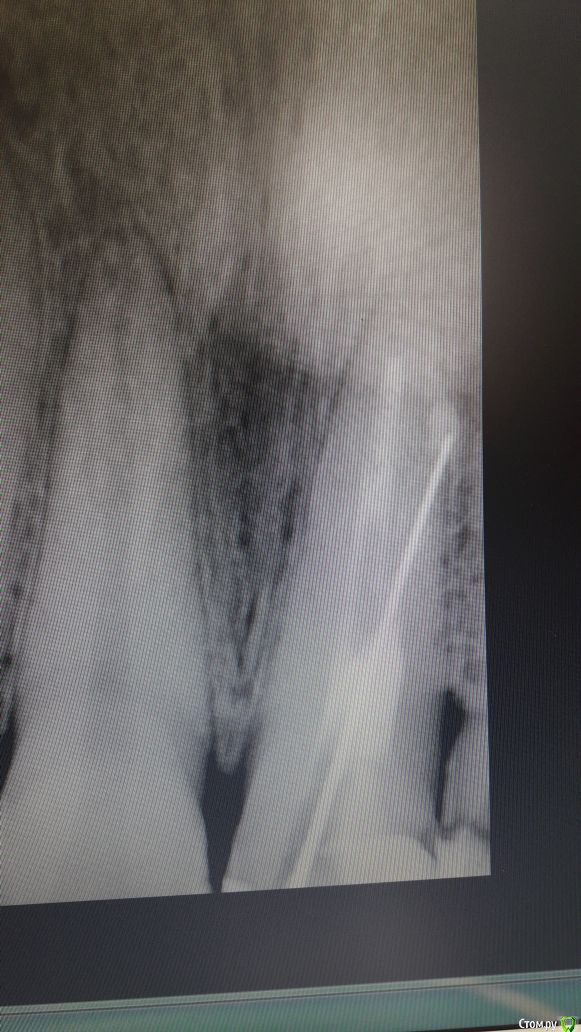

Спустя год-2 опять потемнели зубы. На лечение решилась только недавно. Проконсультировавшись у нескольких врачей решила поставить коронки циркониевые на оба зуба. Так как эндоотбеливание не рекомендовали многие. До лечения был сделан снимок, не смогла прикрепить. Из-за состояния каналов решили их заново прочистить, но из-за материала давалось тяжело. И в какой-то момент мне показалось, что инструмент лезет наружу через десну именно в том месте, где у меня осталось что-то под десной. Врач не мог понять в чем дело. В итоге под рентгеном увидела перфорацию (снимок приложен) с образованием свища. Выходит перфорации 10 лет. Зуб устойчивый, не шатается. Но врач рекомендует удаление и ставить имплант. ((( Так как это мой родной зуб, я не могу вот так вот сразу решится на удаление. Тогда врач начала альтернативное лечение. Пока положила а\б, сказала ходить 3 недели, а затем она введет на место перфорации биодентин. Говорит, что хороший материал, но из-за того, что перфорация застаревшая, не дает гарантий.

post-54986-0-21482400-1524951878_thumb.jpg